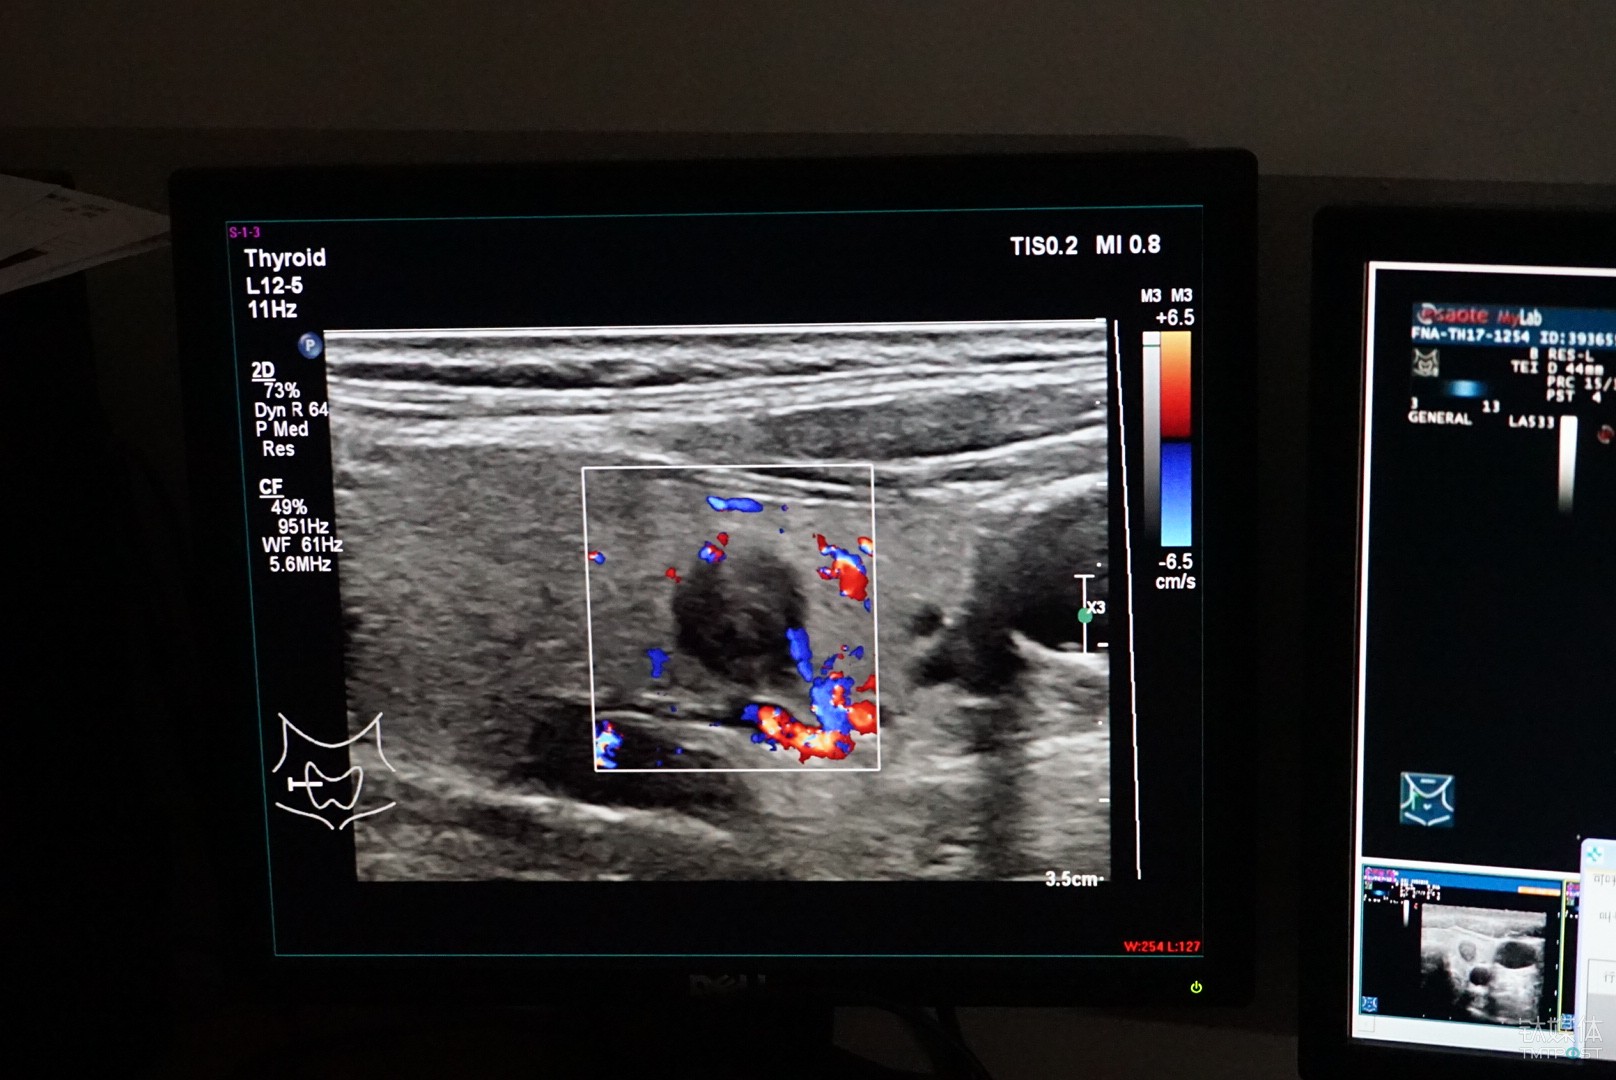

从功能上来说,这是一套基于超声波影象的甲状腺结节良恶性的辅助诊断系统,根据甲状腺结节检查时候拍摄的医学影像的特征,通过对图像的识别和标注,来帮助医生更准确的做出诊断结论。

对于甲状腺结节的检查目前主要依靠超声的方式,相较于CT和核磁,超声的好处是便宜、灵活、无副作用,所以它也是目前临床医学使用最为广泛的一种检测手段,不足之处是图像不清楚、造影比较大,它对医生的要求就比较高。

计算机视觉对图像的处理,传统的机器学习是人为定义特征,由于目前收集到的数据来源于多家医院,标准和规范不统一,德尚韵兴专门采用了一种有监督的深度学习,让医生对数据进行标注,每一个培训的样本都是医生人工标注的,结节的大小、位置,还包括病人的其他的病理特征,之后再反馈给机器进行训练。

根据德尚韵兴总经理胡海蓉提供的,“目前三甲医院医生的平均准确率为60%-70%,基层医院会更加低一些,而辅助诊断系统目前准确率可以达到85%以上,不过由于在我国人工智能还没有行医资格,所以我们将其定位为辅助诊疗,只是给医生提供一些参考。”